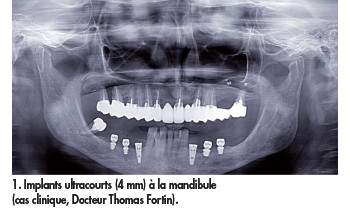

L’European Association of Dental Implantologist, lors de sa 11e conférence de consensus européen (European Consensus Conference) du 6 février 2016 à Cologne, a publié des recommandations cliniques sur l’utilisation des implants courts en prenant soin de considérer, d’une part, les implants courts (de 4 à 8 mm de longueur) et, d’autre part, les implants ultracourts (4 mm) (fig. 1).